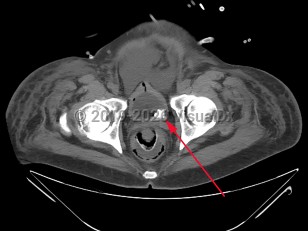

Urinary bladder calculus